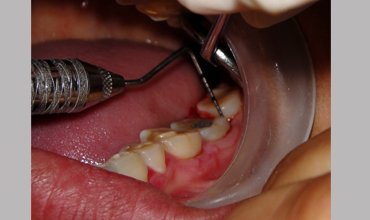

NON SURGICAL MANAGEMENT OF ENDODONTIC LESION AND SURGICAL MANAGEMENT OF PERIODONTIC LESION